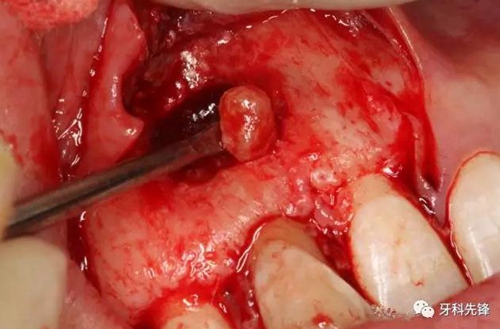

圖9.去除部分唇側(cè)骨板、顯露完整囊壁。

圖10.囊壁完整顯現(xiàn)。